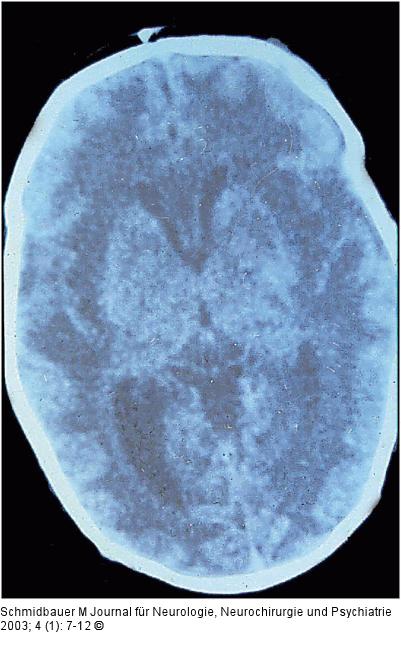

Abbildung 8: Herpes simplex - Enzephalitis CCT einer neonatalen HSV-Enzephalitis mit ausgeprägten, symmetrischen Marklagerdichteminderungen |

Abbildung 8: Herpes simplex - Enzephalitis

CCT einer neonatalen HSV-Enzephalitis mit ausgeprägten, symmetrischen Marklagerdichteminderungen |